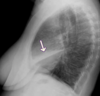

Atelectasia de lóbulo medio con enfisema compensador. Pérdida de volumen del hemitórax derecho.

Atelectasia de lóbulo medio con enfisema compensador. En la proyección lateral se objetiva más claramente el pulmón colapsado.